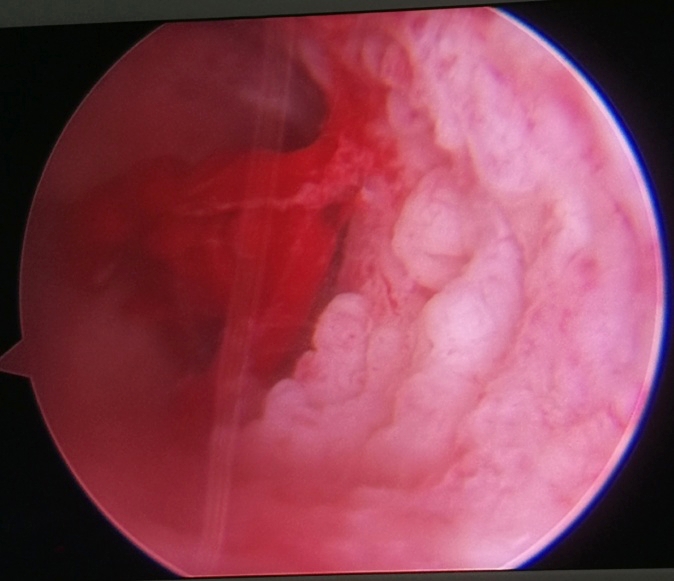

宫腔镜下子宫内膜癌图像